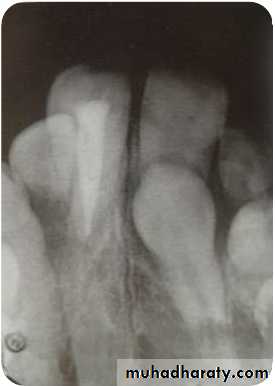

Lateral Cephalogram

Perapical view

First and the most simplest viewAdvantages

1) Root development, pattern and

integrity

2) Crown resorption

3) Root resorption of adjacent tooth

4) Minimum of surrounding tissue is

exposed which increase

accuracy and resolution.

5) Minimal radiation exposure

Disadvantage

1) 2D picture of 3D object

2) cannot determine bucco-lingual

position of tooth & vertical

position of impacted tooth.